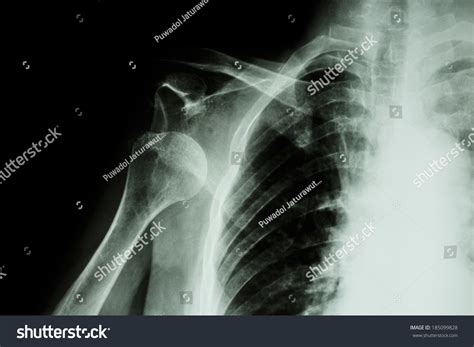

Experiencing a sudden, sharp pain in your shoulder after a fall or a sports-related impact is a distressing ordeal. Often, the first thing medical professionals will order to assess the situation is a Dislocated Shoulder X Ray. Understanding why this imaging is critical, what it reveals, and how it guides your recovery journey is essential for anyone dealing with this common orthopedic injury. A dislocated shoulder occurs when the ball of your upper arm bone (the humerus) pops out of the shoulder socket (the glenoid). Because this area is complex, precise imaging is the gold standard for confirming the diagnosis and ruling out associated complications.

• Visualizing the position of the bones: It confirms whether the humerus is truly out of the socket or if there is a partial dislocation (subluxation).

• Assessing alignment: It helps doctors identify the specific type of dislocation—whether it is anterior (forward), posterior (backward), or inferior (downward).

Following the confirmation provided by the Dislocated Shoulder X Ray, the medical team will proceed with reduction. Once the shoulder is back in its proper position, the doctor will often order a post-reduction X-ray. This second round of imaging is vital to confirm that the bone is correctly seated and that no new fractures were created during the reduction procedure.